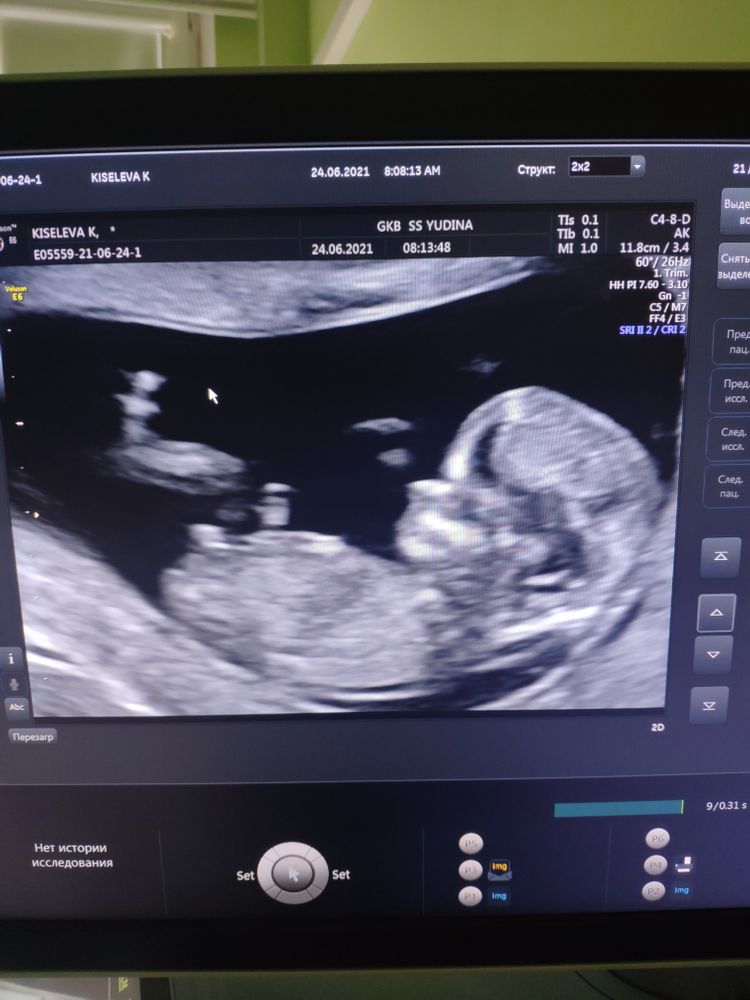

Первый скрининг ждала и столько переживала, 🤔 ведь узи первое я сделала в 6 недель и после этого симптомы исчезали и возвращались 🤢 и я голову себе заморачивала и заморачивала ) моментами даже ощущала будто я не беременна🥳 и хотела уже бежать на платное УЗИ 🤦🏼♀️ но время пришло и все слава богу у нас хорошо🙏🤗

Так ждала пораньше узнать пол ребёночка))) но пока говорят тишина ) знаю нужно смотреть наверное под другим ракурсом 🤭🐣но вдруг тут кто разглядеть сможет, буду рада комментариям ))))

первый спиннинг!! шла с волнением, и желанием встретиться с крошкой. мне предположили мальчика....но надеюсь на второе узи, вдруг предположение не верное и то была например пуповина.))

Если эта белая тоска половой бугорок, то девочка. Но это может быть и ножка, и пуповина)